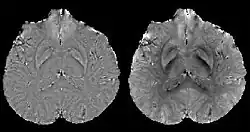

COSMOS solves the inverse problem by oversampling from multiple orientations.[11][12] COSMOS utilizes the fact that the zero cone surface in the Fourier domain is fixed at the magic angle with respect to the B0 field. Therefore, if an object is rotated with respect to the B0 field, then in the object's frame, the B0 field is rotated and thus the cone. Consequently, data that cannot be calculated due to the cone becomes available at the new orientations.

COSMOS assumes a model-free susceptibility distribution and keeps full fidelity to the measured data. This method has been validated extensively in in vitro, ex vivo and phantom experiments. Quantitative susceptibility maps obtained from in vivo human brain imaging also showed high degree of agreement with previous knowledge about brain anatomy. Three orientations are generally required for COSMOS, limiting the practicality for clinical applications. However, it may serve as a reference standard when available for calibrating other techniques.